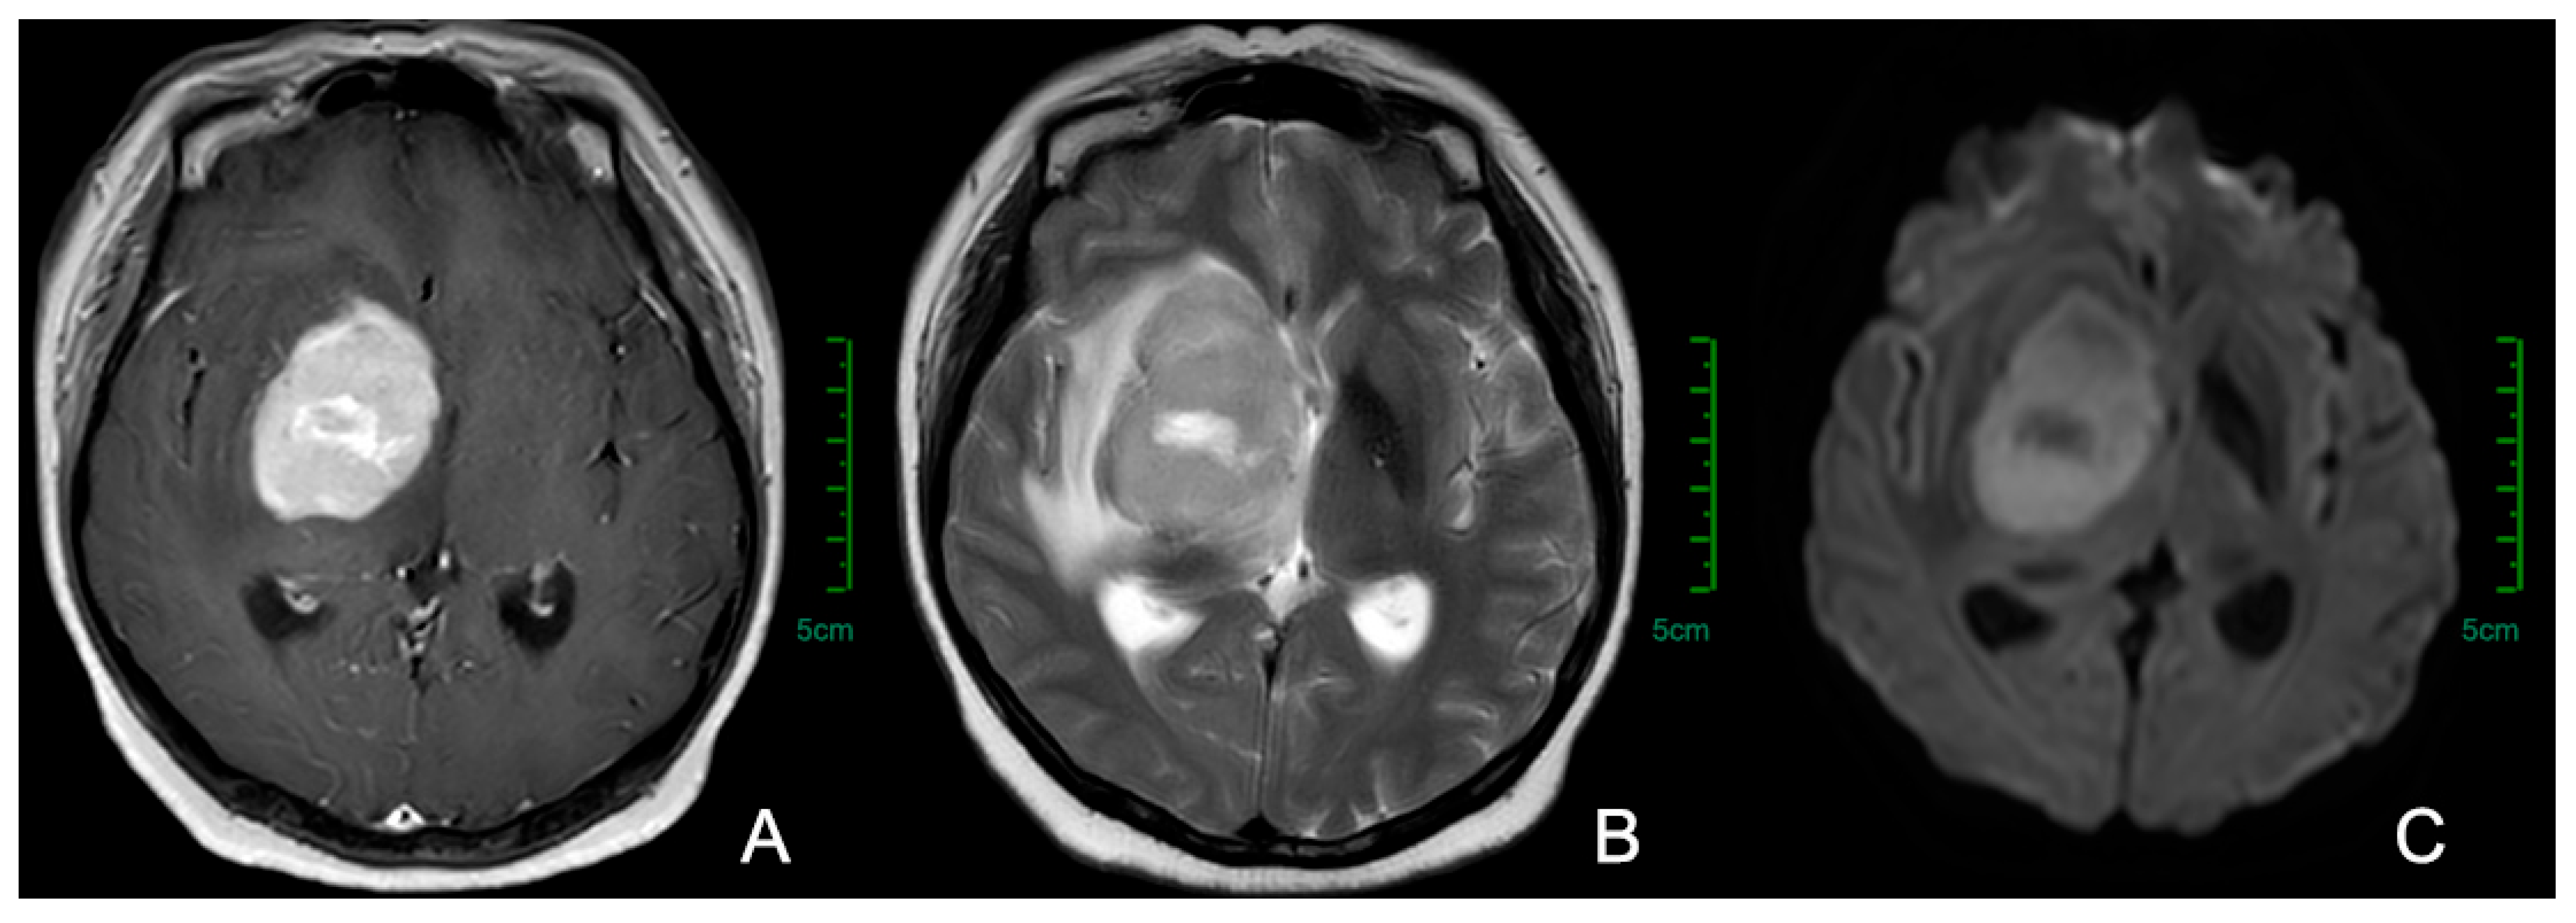

3.2. Imaging Examinations

- Küker, W.; Nägele, T.; Korfel, A.; Heckl, S.; Thiel, E.; Bamberg, M.; Weller, M.; Herrlinger, U. Primary central nervous system lymphomas (PCNSL): MRI features at presentation in 100 patients. J. Neurooncol. 2005, 72, 169–177. [Google Scholar] [CrossRef]

- Barajas, R.F.; Politi, L.S.; Anzalone, N.; Schöder, H.; Fox, C.P.; Boxerman, J.L.; Kaufmann, T.J.; Quarles, C.C.; Ellingson, B.M.; Auer, D.; et al. Consensus recommendations for MRI and PET imaging of primary central nervous system lymphoma: Guideline statement from the International Primary CNS Lymphoma Collaborative Group (IPCG). Neuro. Oncol. 2021, 23, 1056–1071. [Google Scholar] [CrossRef]